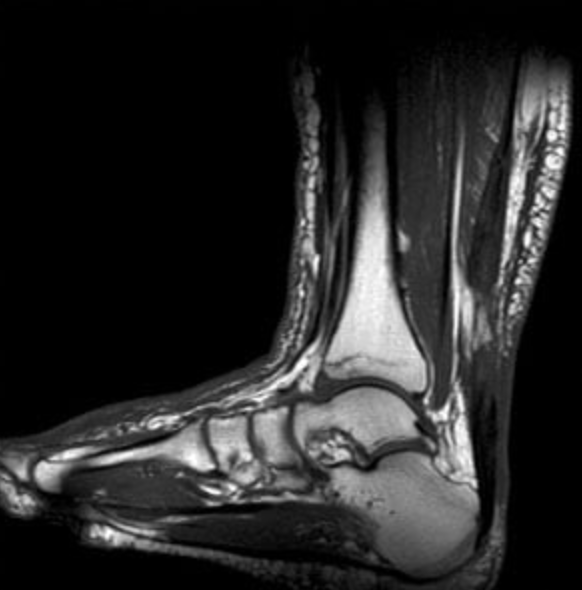

결국 병원에 갔어요. 의사 선생님이 엑스레이를 보시더니 근저족막염이라고 하셨어요. 발바닥 근막에 염증이 생긴 거라는데, 오래 서 있거나 무리한 활동을 하면 더 심해질 수 있다고 하더라고요. 물리치료를 몇 번 받아봤는데, 솔직히 큰 변화는 못 느꼈어요. 매번 똑같은 전기치료만 반복하다 보니 "이게 진짜 나아지는 걸까?" 하는 의문이 들더라고요. 그래서 병원 치료 외에 집에서 할 수 있는 방법이나 다른 대안을 찾아봐야겠다는 생각이 들었어요.